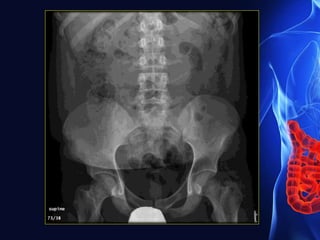

• It occurs when intestinal peristalsis ceases and fluid and

gas accumulate in the bowel loops.

 causes

Paralytic ileus- Supine film